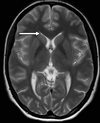

A

right head of caudate nucleus

14